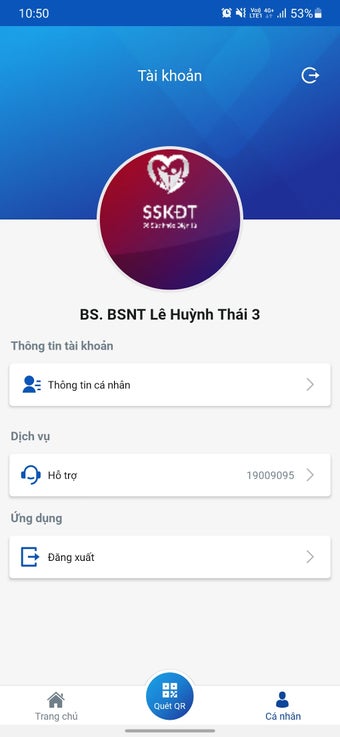

บันทึกข้อมูลสุขภาพอิเล็กทรอนิกส์สำหรับแพทย์เป็นแอปพลิเคชันแอนดรอยด์ที่พัฒนาโดย Văn phòng Bộ Y tế Việt Nam แอปพลิเคชันฟรีนี้ออกแบบมาเพื่อบุคลากรทางการแพทย์และแพทย์เพื่อเก็บข้อมูลผู้ป่วย ทำการฉีดวัคซีน เพื่อลดความแออัดที่จุดฉีดวัคซีน และลดความเสี่ยงในการติดเชื้อ COVID-19 นอกจากนี้ยังช่วยในการแก้ไขปัญหาสุขภาพของประชาชนอย่างรวดเร็ว